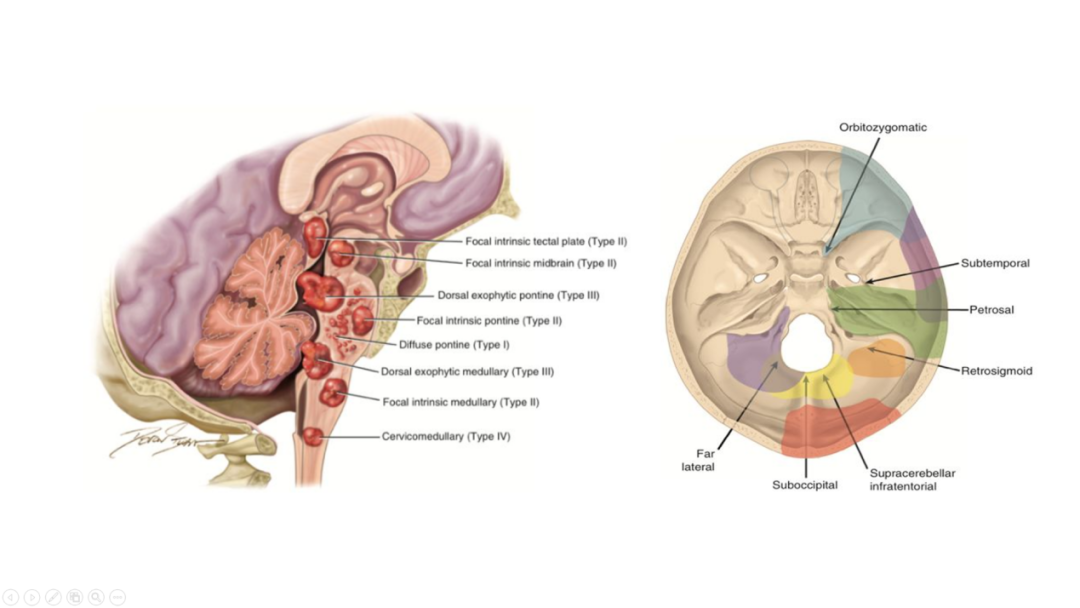

7

大脑深部肿瘤由于其位置深在,周围结构复杂,给手术治疗带来了极大的挑战。脑干是生命中枢所在地,脑干肿瘤手术风险极高。大脑深部肿瘤及脑干肿瘤的显微外科手术治疗是一项复杂而精细的技术,我们通过高超的手术技巧、丰富的临床经验及一流的硬件设备,为这类患者带来个体化的精准治疗,从而达到最佳的治疗效果。